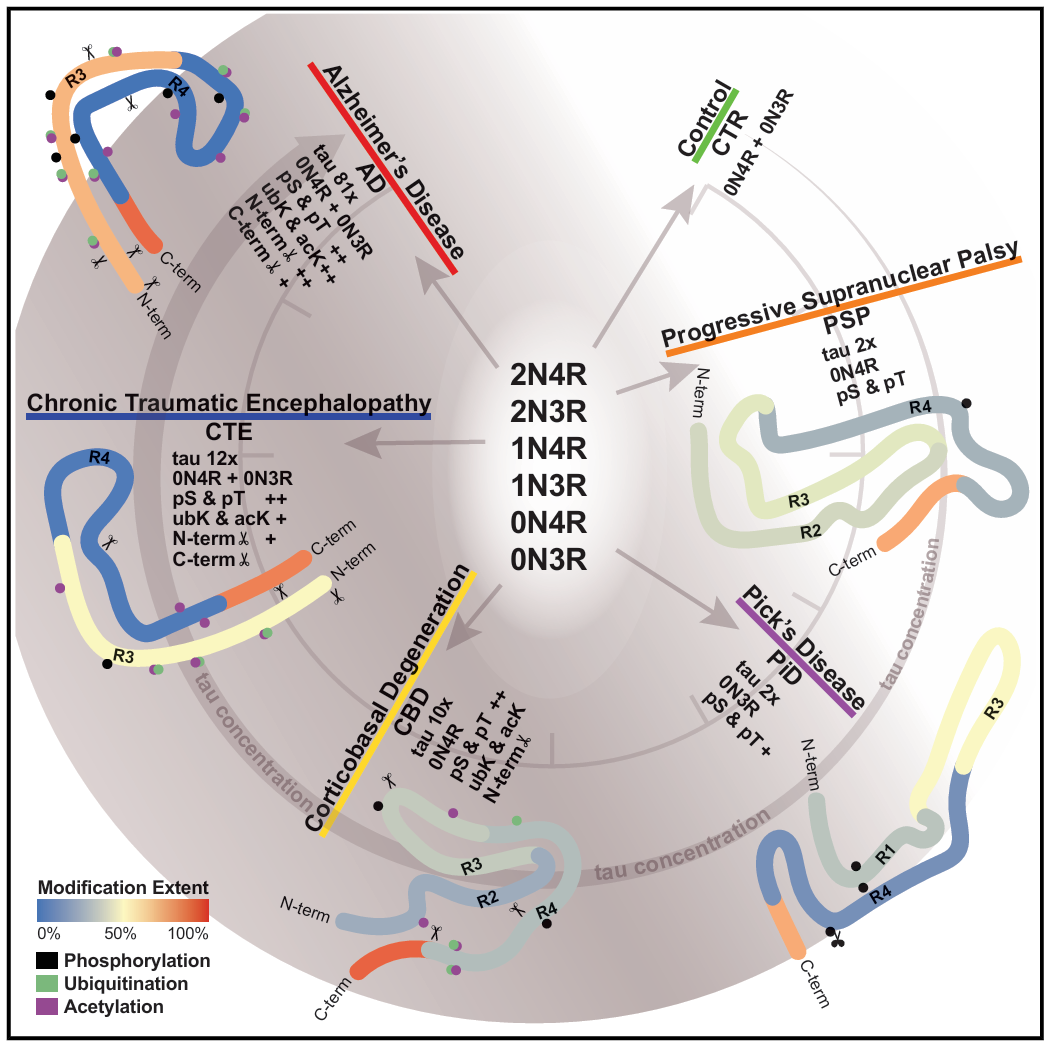

02 (CELL) 人类病理tau蛋白的分子特征区分tau蛋白病相关的痴呆症

2. (CELL,IF:45.5) 人类病理tau蛋白的分子特征区分tau蛋白病相关的痴呆症

02 (CELL) 人类病理tau蛋白的分子特征区分tau蛋白病相关的痴呆症

2. (CELL,IF:45.5) 人类病理tau蛋白的分子特征区分tau蛋白病相关的痴呆症